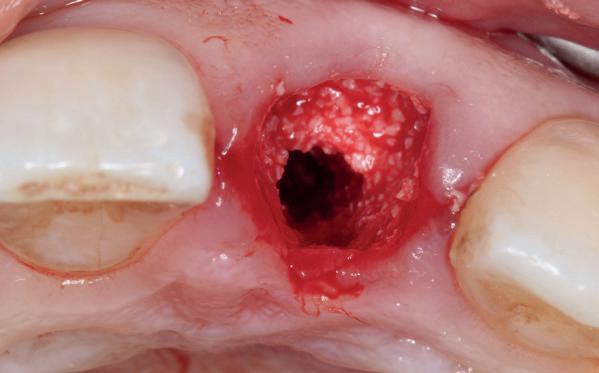

In deze casus is extractie van de 37 geïndiceerd in verband met een fistel en restpockets, zoals zichtbaar op de röntgenfoto’s (afbeelding 1). Duidelijk te zien is de forse peri-apicale ontsteking en het botverlies bij de 37, dat zowel richting buccaal als linguaal doorloopt. De 37 wordt atraumatisch verwijderd. Er is aan de linguale zijde veel bot verloren en er is sprake van een perforatie aan de buccale zijde.

Er wordt besloten om botmateriaal te plaatsen in de extractie-alveole. Vervolgens wordt het afgesloten met een titanium versterkt d-PTFE membraan (afbeelding 2). Na vier weken wordt het membraan verwijderd.

Zes maanden na extractie wordt het implantaat 37 geplaatst. Er is sprake van een goede genezing en de processushoogte en -breedte zijn behouden en opgebouwd. Ook is er zichtbaar gekeratiniseerd weefsel

1 2 Ridge preservation met d-PTFE membranen 35

gewonnen. De wond kan na het plaatsen van een healing abutment primair gesloten worden (Afbeelding 3a-3d).